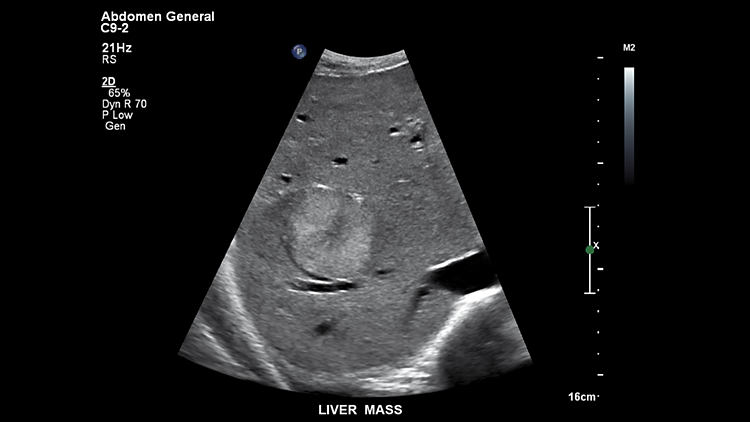

Масса печени, C9-2